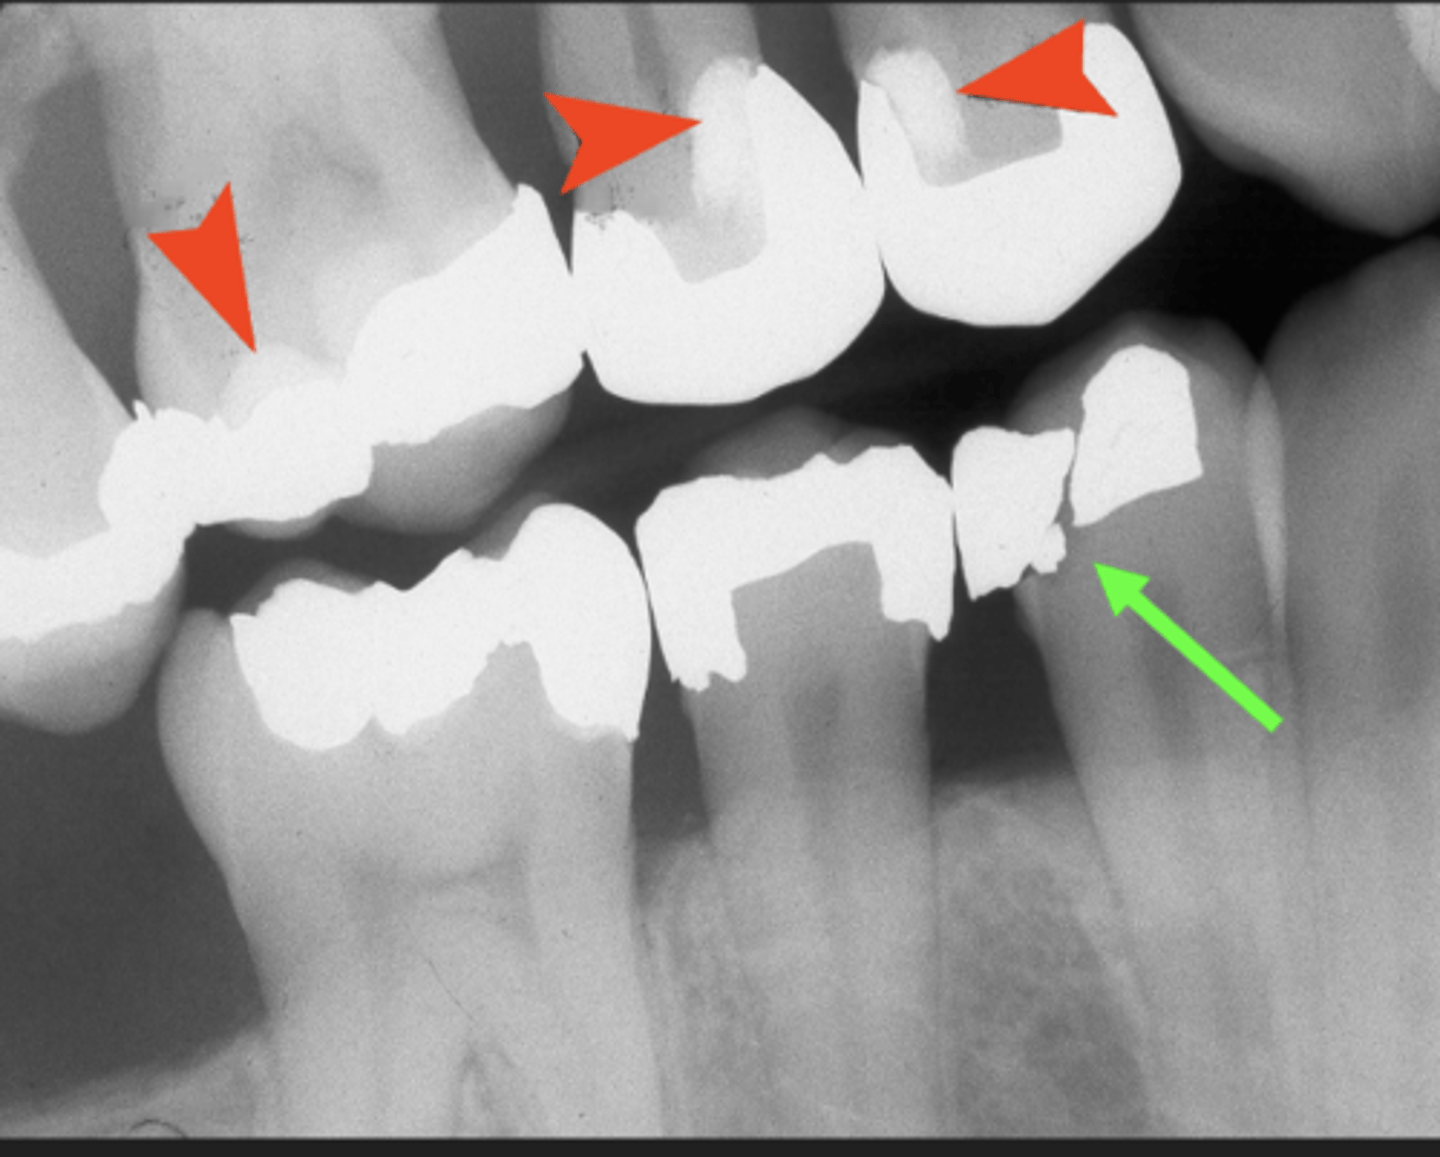

Amalgam restorations

Completely opaque

- One surface amalgam - B,L,O, I

- Multisurface - MO, MOD, ML, OL

- Overhangs

- Amalgam fragments

Amalgam examples

- Overhang and amalgam fragments